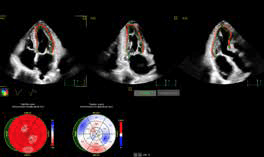

Desde inicios de 2024, Punta del Este recibió al cardiólogo argentino Martín Lombardero, pionero en imagen cardíaca en América Latina. Con el avanzado ultrasonido cardiovascular PHILIPS EPIQ CVx, que integra inteligencia artificial y tecnología 3D, revolucionó los diagnósticos cardíacos, permitiendo prevenir enfermedades de forma inédita. En su libro “El corazón es consciente: Puedes cambiar tu destino cardiológico”, con una narrativa que nos remite al realismo mágico, nos presenta casos médicos en los cuales intervino que nos revelan cómo las emociones pueden sanar o enfermar. Para él, entender el corazón es un viaje profundo hacia el alma y una invitación a escuchar lo que realmente sentimos.